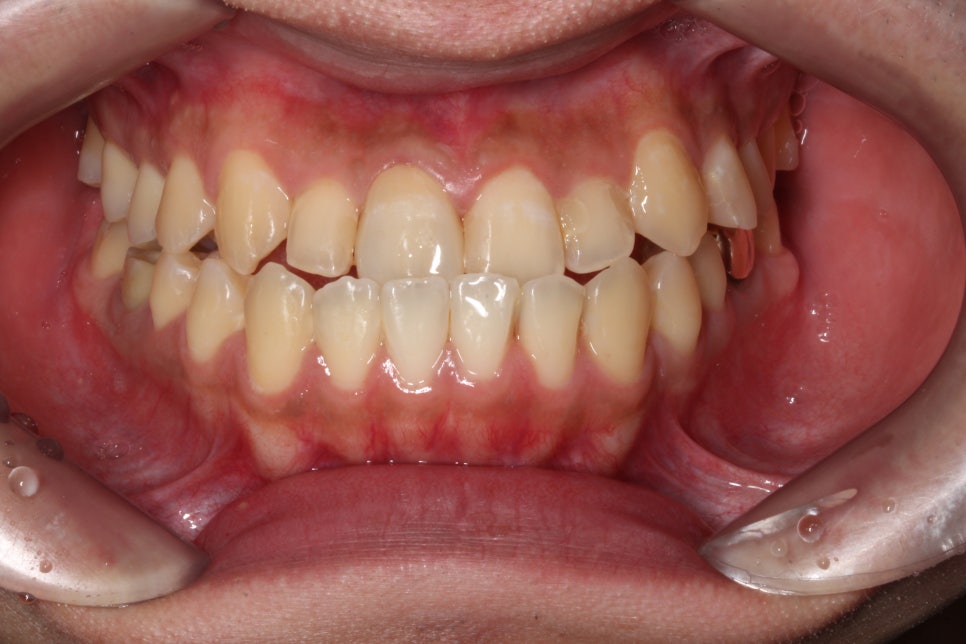

□ 깨진 앞니

출처:투디 치과/ 깨진 앞니 사례의 블링스 전후 사진입니다.